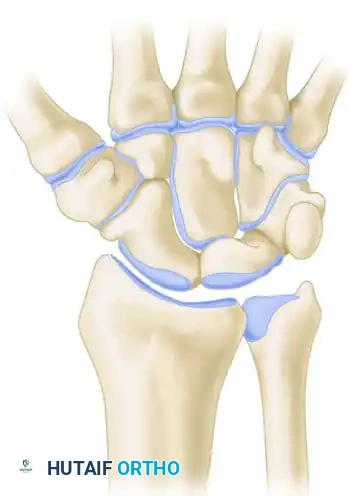

1. Routine Radiography

The initial evaluation must always include four standard views:

* Posteroanterior (PA): Assesses carpal arcs (Gilula's lines), ulnar variance, and joint space narrowing.

* Lateral: Evaluates carpal alignment (collinear relationship of the radius, lunate, and capitate) and measures the scapholunate angle (normal 30°-60°) and capitolunate angle (normal <15°).

* Oblique: Excellent for visualizing the scaphotrapezial joint and the dorsal aspect of the triquetrum.

* Scaphoid View: A PA view with the wrist in ulnar deviation and slight extension to elongate the scaphoid and identify occult waist fractures.

* Instability Series / Fluoroscopy: Patients with suspected ligamentous instability require dynamic imaging (clenched fist views, radial/ulnar deviation views). Abnormal motion, widening of the SL interval (>3mm, "Terry Thomas sign"), or palpable popping must be reproduced and observed fluoroscopically.

* CT Scan: The gold standard for evaluating osseous anatomy, fracture union, and preoperative planning for intra-articular distal radius fractures.

* MRI: Highly sensitive for occult fractures, avascular necrosis (Kienböck's or Preiser's disease), and intrinsic ligament or TFCC tears.

* Wrist Arthrogram: Historically used for ligamentous tears, though largely supplanted by high-resolution 3T MRI. It remains useful when combined with fluoroscopy or MRI (MR Arthrography) to detect subtle capsular or cartilage defects.